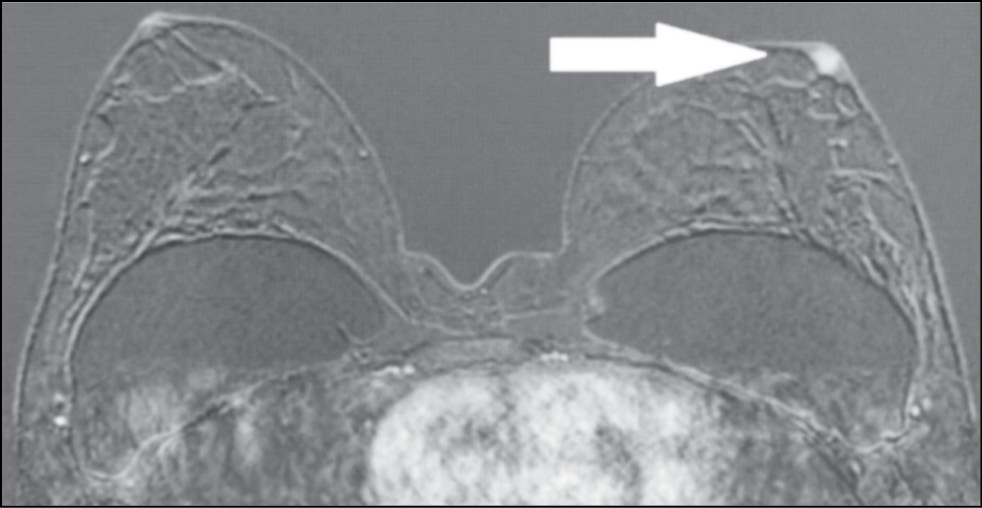

A 59-year-old patient complained of erosive changes in the nipple (Fig. 1). Physical examination revealed erythema, erosion, and nipple retraction. Doppler ultrasonography with color flow mapping revealed increased blood flow in the nipple projection (Fig. 2). Mammography findings were normal. To assess the extent of disease spread, breast MRI with contrast enhancement was performed. The early postcontrast series (Fig. 3) and maximum intensity projection (MIP) images (Fig. 4) showed a segmental contrast retroareolar area from the nipple level to posterior breast sections. Ultrasound-guided core biopsy followed by immunohistochemical analysis revealed Paget’s disease of the nipple with high-grade intraductal carcinoma in situ. Receptors for estrogen (G3 ER) and progesterone (PR) were negative. Oncogenic protein Ki-67 was 45%.

Figure 4. Magnetic resonance imaging of Paget’s disease (maximum intensity projection): the retroareolar area of segmental enhancement from the nipple level to the posterior breast (arrow).